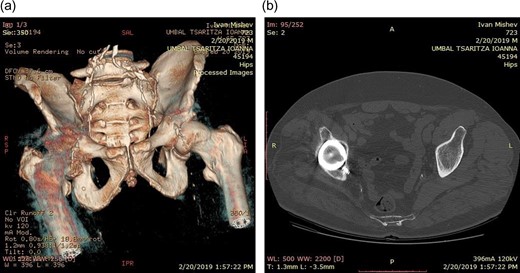

Life-size 3D model was printed from a converted file containing the computed tomography (CT) scan of one patient with severe acetabular defects waiting for total hip revision surgery. The 66-year-old male had a background of coxarthrosis. He underwent total hip arthroplasty of his right hip in February 2017. The preoperative CT scan and X-Ray of the pelvis showed large right-sided pelvic defect and severe acetabular defect (Figs 1 and 2). The patient had history of cardio-vascular comorbidity and underwent 2 week specific antihypertensive therapy preoperatively.

Preoperative radiograph demonstrating large acetabular defect with screw penetration.

We started with rapid prototyping: high resolution protocol with a slice thickness of 1 mm was used to achieve maximal image quality. The CT scan was converted and imported to 3D Slicer, imaging processing software (IPS). Using the IPS we treshholded the image, achieving differentiation of the pelvis and hip from the surrounding soft tissue. We digitally segmented the pelvis by deleting pixels, representing additional bony contact. The right side of the pelvis was isolated. The segment of interest was saved in.stl-format (stereolithographic format), suitable for the 3D printer we used, in our case a Formlabs 2. The.stl-format allows instructions related to the shape, thickness, and texture of the 3D image to be communicated to the 3D printer [3]. Our patient needed 3D planning of the acetabular reconstruction only, as the femur had normal shape. The 3D model enabled visual assessment of the complex acetabular deformity. Given the complexity of our case, the hemipelvis model allowed a life-size anatomical representation of the operative field. (Fig. 3)